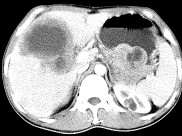

- 单项选择题女,61岁, 上腹部疼痛1个月,食欲减退, 消瘦,CT所见如图, 最可能的诊断为( )

A、原发性肝癌

B、肝包虫病

C、肝转移瘤

D、胃癌肝转移

E、肝脓肿